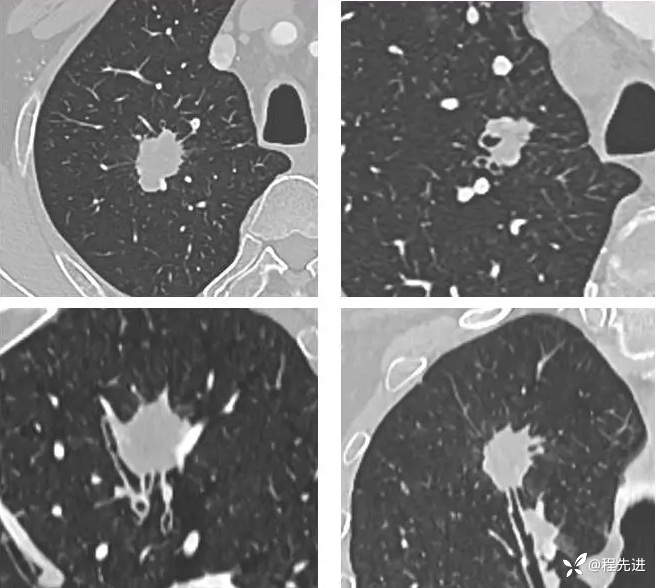

患者性别:男

患者年龄:70岁

简要病史:因“体检发现肺结节10余天”入院,患者平时无明显咳嗽、咳痰,胸闷胸痛咯血、呼吸困难

既往史:吸烟40年,平均每天30支;戒烟10年。高血压、糖尿病。

指脉氧 97% 一般情况可,其他阴性,实验室检查:NSE:20.56 ng/ml↑